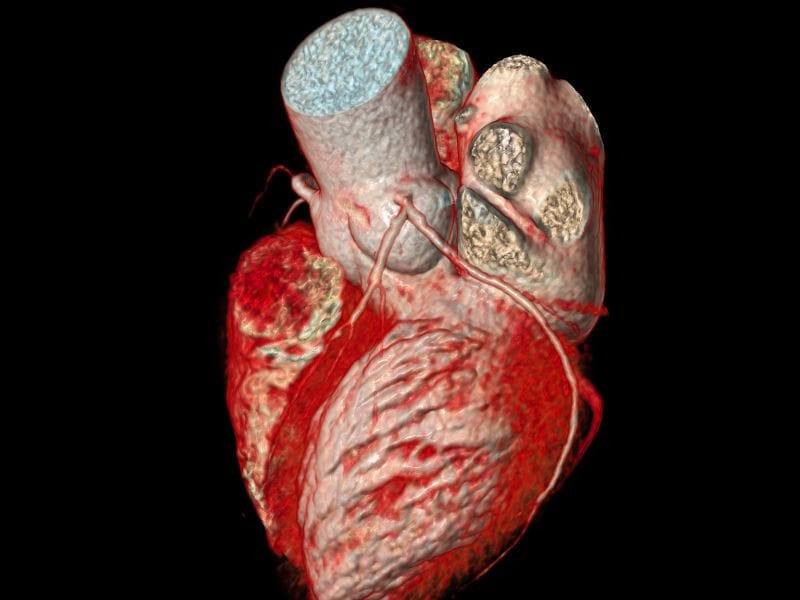

Exame de Doppler em São José, SC: o que você precisa saber A Clínica Simi, localizada em Florianópolis, é referência no atendimento médico especializado em diversas áreas, incluindo o exame de Doppler. O exame de Doppler é um procedimento não invasivo que utiliza ondas sonoras de alta frequência para avaliar o fluxo sanguíneo em diferentes […]

Exame de Doppler em Florianópolis: o que você precisa saber O Exame de Doppler é um procedimento médico não invasivo que utiliza ondas sonoras de alta frequência para avaliar o fluxo sanguíneo em diferentes partes do corpo. Em Florianópolis, a Clínica Simi oferece esse exame com qualidade e precisão, ajudando a diagnosticar e monitorar diversas […]

O exame de Doppler é um procedimento não invasivo que utiliza ondas sonoras de alta frequência para avaliar o fluxo sanguíneo em diferentes regiões do corpo. Em Biguaçu, SC, esse exame é fundamental para diagnosticar e monitorar uma série de condições vasculares, como varizes, trombose venosa profunda, insuficiência arterial e aneurismas. Por que fazer o […]